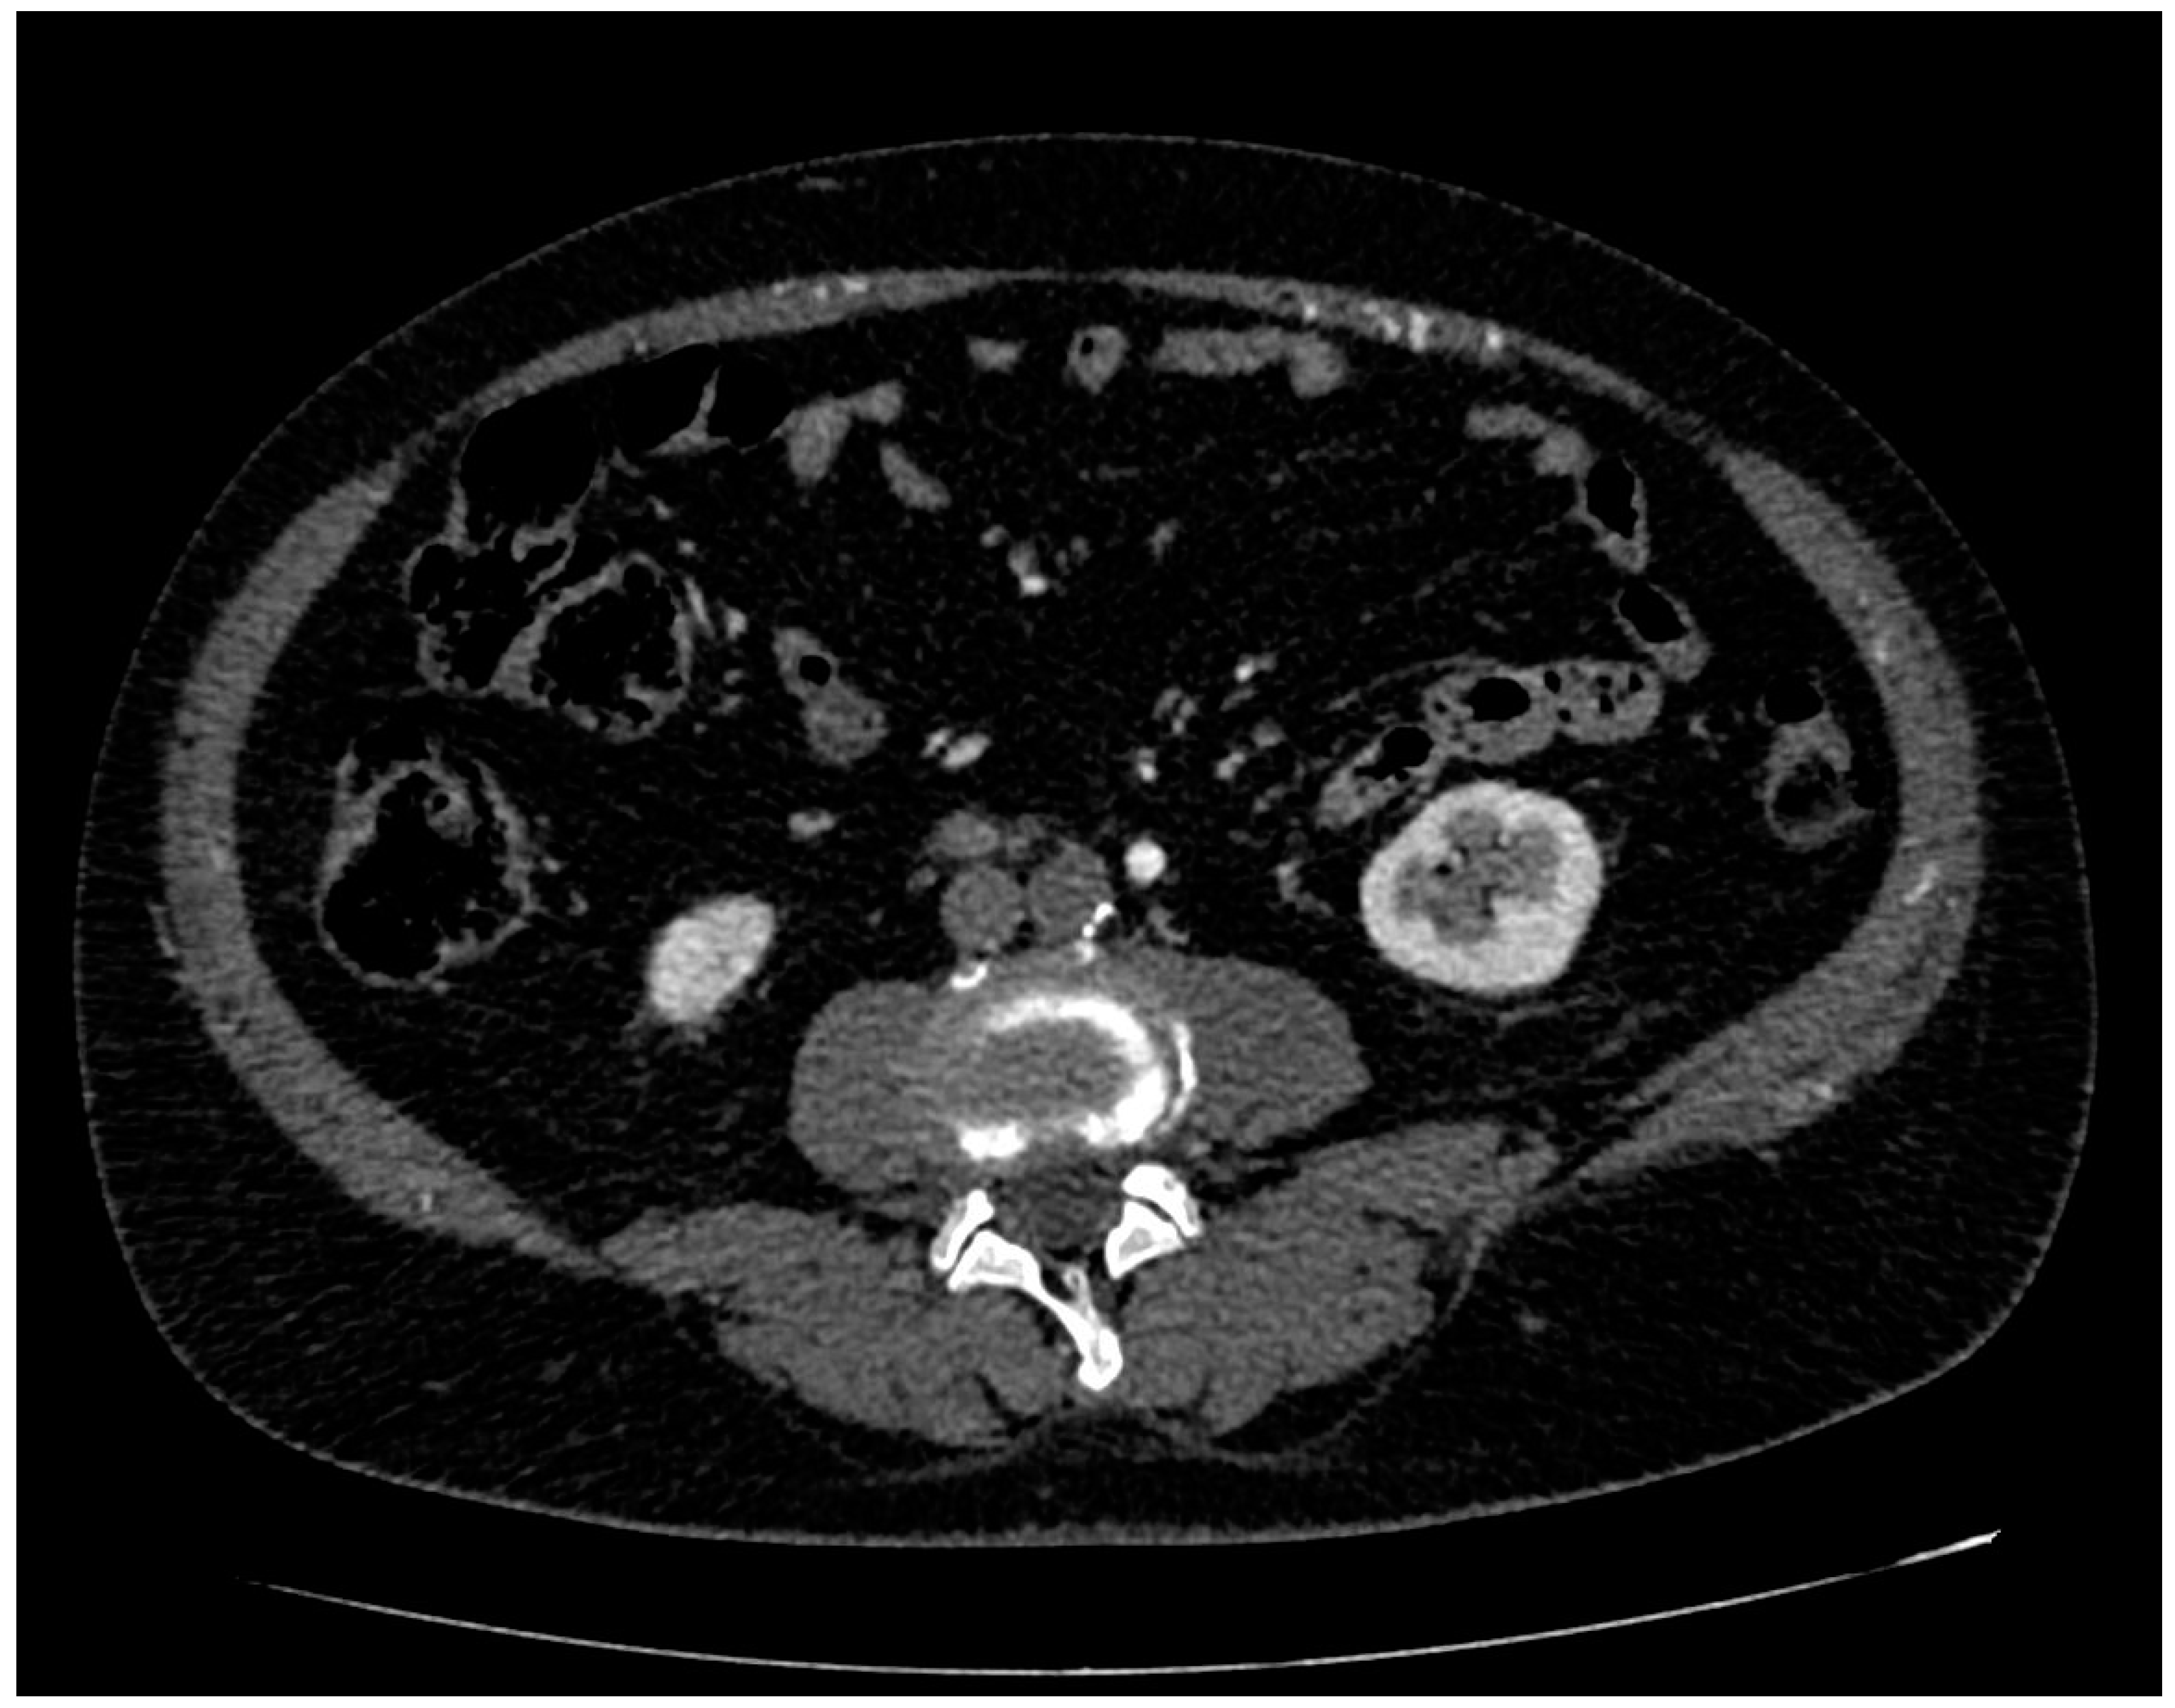

- Focal ischemia of the left renal parenchyma in four patients (36.4%) (Figure 3);

- Focal ischemia of the splenic parenchyma in two patients (18.2%) (Figure 4);